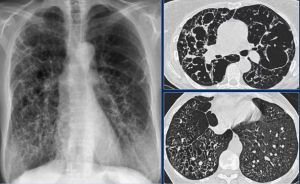

Идиопатический легочный фиброз (ИЛФ) - специфическая форма хронической фиброзирующей интерстициальной пневмонии, характеризующаяся неизвестной причиной возникновения, отсутствием внелегочных проявлений, гистологической картиной обычной интерстициальной пневмонии (ОИП), а также рентгенологическим паттерном ОИП (широко известным под названием «сотовое легкое»).

Всем пациентам с подозрением на ГП рекомендуется проведение КТ органов грудной полости для определения характера изменений в легочной ткани, подтверждения диагноза ГП и дифференциальной диагностики с другими ИЗЛ. Различные комбинации рентгенологических признаков формирует КТ картину (паттерн) ГП. В настоящее время принять выделять три основных КТ картины ГП - типичная, вероятная, неопределенная, которые различаются при нефибротиче- ском и фибротическом фенотипах.

Типичная картина нефибротического ГП включает такие изменения легочной паренхимы, как матовое стекло, мозаичная плотность легочной ткани, а также признаки патологических изменений со стороны мелких дыхательных путей (плохо очерченные центрилобулярные очаги, воздушные ловушки).

Типичная картина фибротического ГП включает характерные признаки ГП и признаки фиброза легочной ткани: ретикулярные изменения, нарушающие легочную архитектонику (нормальное расположение сосудов и видимых бронхов) и/или тракционные бронхо- эктазы; +/- сотовое легкое; хаотичное распределение фиброзных изменений (без отчетливого преобладания) или преобладание в средней легочной зоне (на уровне корней), характерна большая воздушность нижних легочных зонСаркоидоз - системное воспалительное заболевание неизвестной этиологии, характеризующееся образованием нека- зеифицирующихся гранулем, мультисистемным поражением различных органов и активацией Т-клеток в месте гранулематозного воспаления с высвобождением различных хемокинов и цитокинов.

Неспецифическая интерстициальная пневмония (НСИП) - это одна из разновидностей ИИП, характеризующаяся наличием симптома «матового стекла» на КТ, преобладанием изменений в субплевральных и базальных отделах легких, образованием участков консолидации и ретикулярными изменениями, редким формированием тракционных бронхоэктазов и отсутствием или незначительным распространением пневмофиброза.